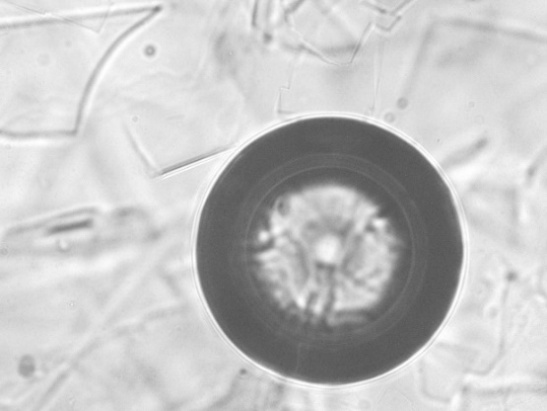

Dark field microscopy

The formed liposomes were seen under Magnus INV manufactured by Olympus Optosystems at magnifications of 10X and 40X with inverse phases for better viewing.

Fig. 8: Image of liposome under darkfield microscope 40X and 10X, respectively

Images under dark field microscope

Optimized batch B3 under a dark field microscope had been viewed in inversed phase to view the interior of the liposomes in 40X and 10X, respectively. Instrument used Magnus INVS (220-240V-0.3A, 50-60Hz). The liposomes were regular and spherical.